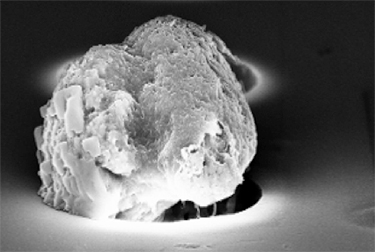

But scientists do know that circulating tumor cells (CTCs) are one of the keys to metastasis. Like migrants, invaders, or colonizers from nation-states seeking to expand, CTCs leave the primary tumor, travel through the body’s vasculature, and somehow serve as seeds for cancer’s spread.

It’s become more and more evident, he says, that the fluid base of cancer progression is not as simple as previously thought. The circulating population of cells originally thought to be tumor cells includes a mixture of epithelial-derived cells that are not all cancer cells but likely play a role in the process and may have independent prognostic potential. CTC enumeration has offered many new perspectives on the process of metastatic progression. The simplistic notion that a single cell leaves a tumor, enters the bloodstream, and then exits at the next available opportunity and forms a metastasis does not appear to be the case at all, Dr. Boffa says. “There’s much more to the circulation than just a simple downstream flow pattern, and CTC study has exposed flaws in this model and has real potential to clarify the true pathway.”